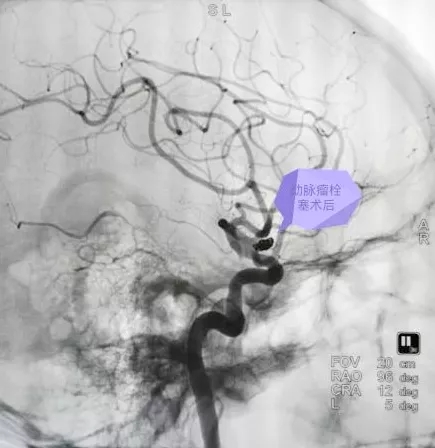

(术后影像资料)

目前,颅内动脉瘤的治疗方法主要有两种,即开颅动脉瘤夹闭和经血管内介入栓塞,这两种方法都属于高难度、高风险的四级手术。周小荔副主任与家属充分沟通并组织全科医师进行了充足的讨论后,认为应避免开颅手术创伤较大的手术风险,微创、创伤小、恢复快、并发症低的介入治疗是患者的最佳选择。积极完善术前准备后,在兰大二院孙守元副教授指导下,神经外科一病区团队成功完成“颅内动脉瘤栓塞术”,术后患者神志逐渐转清,目前患者恢复良好,现已康复出院。